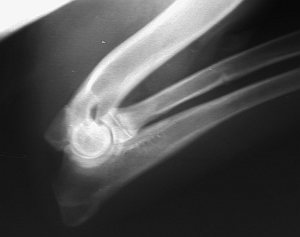

Ellenbogengelenk (ML)  Hund gebeugt In den letzten Jahren werden bei jungen Hunden als Lahmheitsursache im Bereich der Vordergliedmassen immer häufiger Erkrankungen des Ellbogengelenkes diagnostiziert. Es handelt sich meist um chronische degenerative Arthropathien, die in den weitaus meisten Fällen ihre Ursache schon in Erkrankungen des Gelenkes während der Wachstumsphase beim jugendlichen Hund haben. Durch Wachstumsstörungen im Bereich der Gelenkflächen oder in den Wachstumszonen der gelenkbildenden Knochen kommt es zu Inkongruenzen oder/und Instabilitäten, die im weiteren Verlauf, je nach Ausprägungsgrad, zu mehr oder minder erheblichen Arthrosen führen. Die Arthrosen können wie bei dem Gelenk als Folge von speziellen Erkrankungen (Grunderkrankungen) entstehen. Sie können aber auch auftreten, wenn solche Grunderkrankungen nicht vorliegen.

Zu den Grunderkrankungen, die diese Arthrosen verursachen, zählen :

- isolierter Processus anconaeus (IPA)

- fragmentierter (isolierter) Processus coronoideus medialis ulnae (FCP),

- Osteochondrose des Condylus medialis humeri (OCD, selten beim DSH, häufiger sekundäre Usuren bei FCP)

- Inkonguenz/Stufenbildung und andere Anomalien des Gelenkknorpels

Obwohl medizinisch nicht korrekt, werden diese Erkrankungen unter dem Begriff „Ellbogengelenksdysplasie (ED)“ zusammengefasst. (Quelle: SV e.V.)